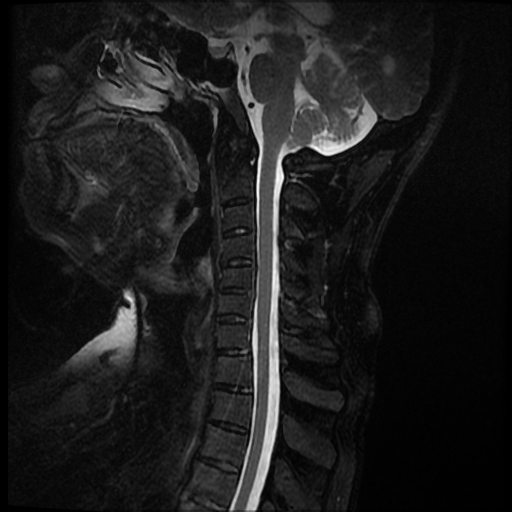

La espondilitis anquilosante (EA), es una enfermedad autoinmune inflamatoria crónica que afecta principalmente a las articulaciones de la columna vertebral y causa dolor crónico severo, afecta principalmente a las articulaciones de la columna, las articulaciones sacroilíacas y los tejidos blandos adyacentes, como los tendones y los ligamentos. En casos más avanzados, esta inflamación puede dar lugar a fibrosis y calcificación, dando como resultado la pérdida de flexibilidad y la fusión de la columna, asemejándose a un “bambú” con una posición inmóvil. Este caso se enfoca a paciente de 37 años de edad, que manifiesta rigidez y perdida de la linealidad de la columna cervical, encontrando a través del estudio de MRI calcificación de los ligamentos anterior y posterior de la columna cervical, más fusión de vértebras cervicales.

Ankylosing spondylitis (AS) is a chronic inflammatory autoimmune disease that primarily affects the joints of the spine and causes severe chronic pain. It primarily affects the joints of the spine, the sacroiliac joints, and adjacent soft tissues such as tendons. and the ligaments. In more advanced cases, this inflammation can lead to fibrosis and calcification, resulting in loss of flexibility and fusion of the spine, resembling a “bamboo” with an immobile position. This case focuses on a 37-year-old patient, who manifests rigidity and loss of linearity of the cervical spine, finding through the MRI study calcification of the anterior and posterior ligaments of the cervical spine, plus fusion of cervical vertebrae.

Se observa perdida de la lordosis normal de la columna cervical.

Se observa hipo intensidad del ligamento longitudinal anterior y posterior de la columna cervical, también se observa perdida de la movilidad y rigidez de la misma, los ligamentos interespinosos se ven hipointensos en T2 y en T1, al igual que el pliegue nucal, lo que sugiere calcificación de estas estructuras anatómicas.

Se observa fusión de las vertebras cervicales 5-6 y 6-7, dando la apariencia de bambú.

• Perdida de la lordosis

• Ligamentos espinales anterior, posterior, interespinosos y pliegue nucal calcificados

• Fusión de vertebras cervicales 5-6 y 6-7.

Dentro del estudio imagenológico con diferentes técnicas, es importante mencionar que es de utilidad un protocolo específico para espondiloartropatías en el caso de RM, ya que se busca detectar edema de estructuras afectadas, siendo un protocolo útil en la evaluación de la columna vertebral la secuencia ponderada en T1 TSE junto a una secuencia de inversión-recuperación de tiempo corto (STIR). Debe ser empleada una matriz de 512 pixeles, con un grosor de corte de 3 a 4mm, adquirida con un resonador de 1,5Tesla. La administración de gadolinio asociada a secuencias con saturación grasa T1 turbo spin eco se requieren para una mejor evaluación de algunos aspectos, como por ejemplo la entesitis, según la experiencia de algunos autores, al igual que la evaluación de abscesos asociados a la espondilodiscitis séptica, para la evaluación de tejido necrótico, ver la extensión de masa de partes blandas y el realce discal. También son útiles las secuencias STIR, particularmente en la evaluación de articulaciones costovertebrales.